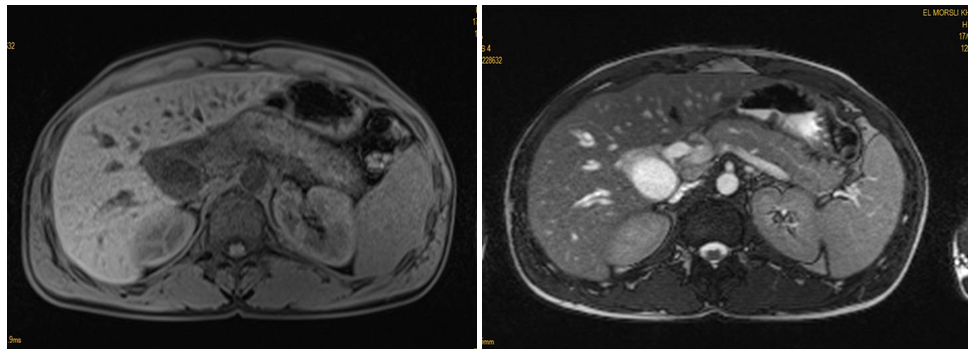

The biological assessment had objectified: a hemoglobin at 12.9g/L; number of leukocytes at 5230/mm3; 3260 neutrophils (62.3%); eosinophils: 230 (4.4%) (reference range: 40-500); total bilirubin 19.9mg/dL; alkaline phosphatase at 425U/L; gammaglutamyl transferase at 80U/L; ASAT at 225 U/L; ALAT at 376U/L. Lipaemia was at 122 (<3 times normal). Hepatitis serology and serum IgG 4 assay were negative. The abdominal ultrasound had shown a swollen pancreas in its cephalic portion with dilation of the intra- and extra hepatic bile ducts. The magnetic resonance cholangiography (BILI-MRI) had objectified a swollen aspect of the head of the pancreas which arrives in contact with the superior mesenteric vein without signal anomalies. It also showed significant dilation of the main bile duct and the intrahepatic bile ducts without vascular invasion and without dilation of the pancreatic ducts (Figure 1).

Figure 1 Bili-MRI: showing a swollen head of the pancreas with significant dilation of the main bile duct and the intrahepatic bile ducts.